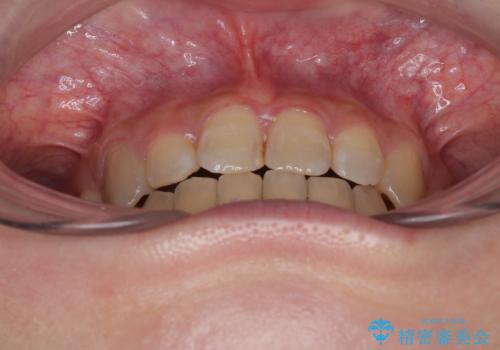

- 上下の八重歯を気にして来院された患者様です。

非抜歯矯正で歯列を整えると、治療後に口元が今よりも突出する可能性が高かったため、上下左右の小臼歯4本を抜歯し、ワイヤー装置にて矯正治療を行うこととしました。

第二小臼歯抜歯の治療となったため、やや時間はかかりましたが、概ね予想通りの期間で治療を終えることができました。